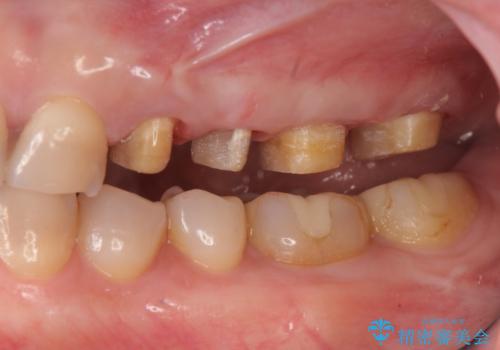

放置した虫歯 根管治療 フルジルコニアクラウン

- 虫歯治療を途中で中断し放置した歯の治療再開を希望され来院されました。

樹脂やクラウン・銀歯の老朽化がみられるため、丁寧に除去を行い根管治療を行ったのち、歯軋り・厚みの少なさを鑑みフルジルコニアクラウンによる補綴を計画します。

治療を途中で中断するとよりより虫歯の進行が加速したり最悪歯を残すことが難しくなることもあります。